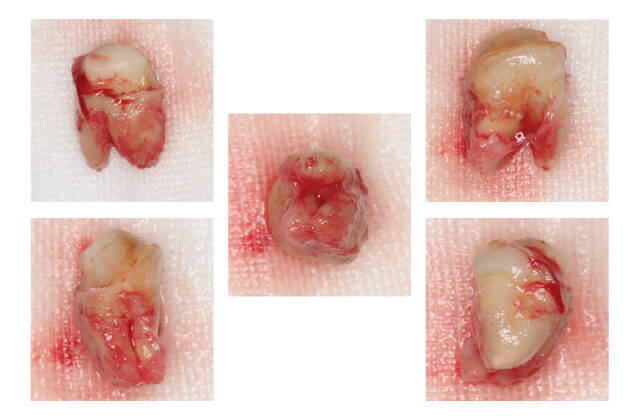

エンドサージェリー治療例 3

(一度患歯を抜いて口腔外で病巣部を切除し薬剤を填入した後に元の場所に戻す外科的治療)